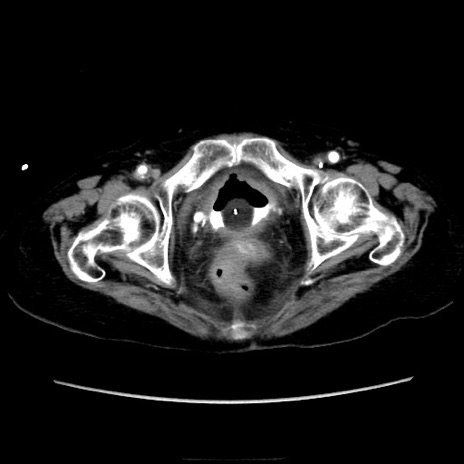

症例40(横断像)

横断像